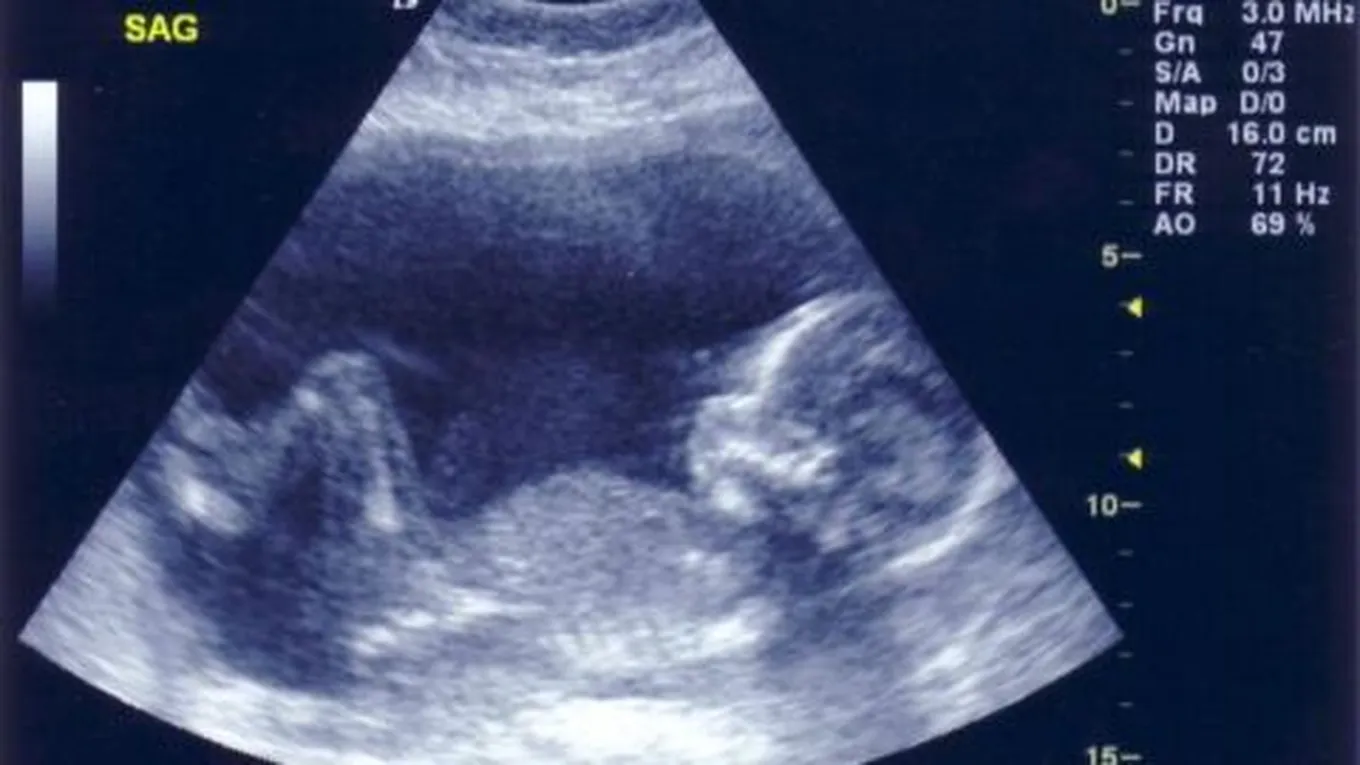

- أضمن طريقة لمعرفة نوع الجنين بدقّة هي فحص الأيكو أو السونار عند الطبيب، وهو عبارة عن موجات صوتية يُصدرها جهاز السونار تدخل هذه الموجات داخل بطن المرأه و وعند الاصطدام بجسم ما ترتدّ هذه الموجات، وهذه الموجات لا تكون ضارّة سواء بالجنين أو المرأة الحامل، وعندها يستطيع الطبيب رؤية الجنين ومعرفة قياساته وحجمه وتستطيع الموجات أن تعرف وتحدّد الأعضاء التناسلية لهذا الجنين وبالتالي معرفة إذا كان ذكراً أم انثى.